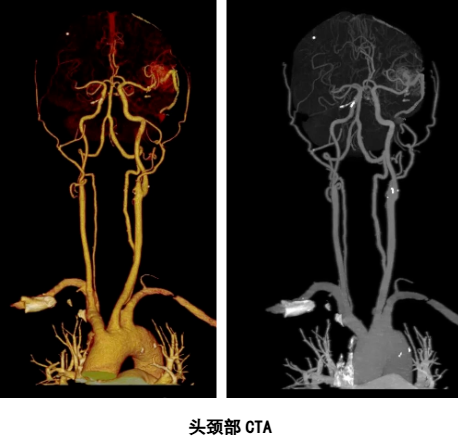

头颈部CTA检查:

(1)脑血管疾病,如动脉瘤、动静脉畸形、动脉狭窄和闭塞、脑梗塞、脑出血、烟雾病、动脉炎、脑动脉支架和搭桥术后评估、静脉窦血栓等;

(2)颈部血管疾病,如颈动脉和椎动脉斑块和狭窄、颈动脉体瘤和颈静脉球瘤、假性动脉瘤、颈动脉夹层,静脉狭窄、曲张和血栓等;

(3)颈动脉手术术前定位、颈动脉支架置入术后效果判定,血管介入手术的评估及随访等;

(4)高危病人的筛查(如高血压、糖尿病、冠心病、高脂血症、肥胖、吸烟);

(5)出现头痛、头晕、手麻、肢体无力等症状的患者。